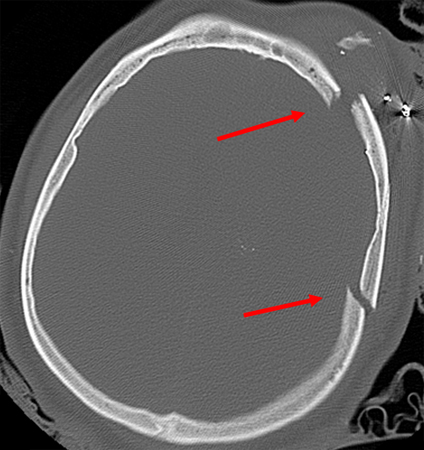

Comminuted depressed fracture of the frontal sinus with air, fluid, and bone fragments in frontal sinus and pneumocephalus; level of depression greater than width of cortex

From the teaching collection of Demetrios Demetriades; used with permission